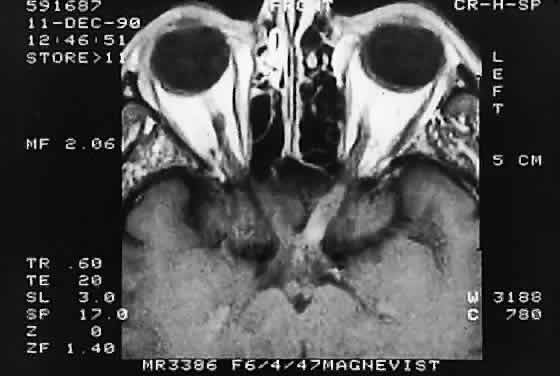

Modern imaging techniques have greatly facilitated the evaluation of optic nerve sheath meningioma and glioma.29 Plain orbital radiographs occasionally show abnormalities of the optic foramen and calcification. Imaging studies (CT and MRI) show diffuse tubular or less commonly, globular enlargement of the nerve sheath complex (Fig. 43).49,50 As with its intracranial counterpart, the optic nerve meningioma typically enhances brightly. “Tram-tracking” results when the thickened sheath outlines the uninvolved central nerve from which it is sharply demarcated. Although characteristic of optic nerve meningioma, this is not specific and can be seen in inflammatory conditions and rarely even in optic nerve glioma. Precise localization of the extent of the tumor is determined with MRI studies, particularly with fat-saturation techniques. Dilation of the anterior perioptic space (perioptic cyst) between the anterior edge of the tumor and the globe is seen in instances in which the tumor does not encroach on the globe and is a distinct and common feature.51,52

Fig. 43. Primary meningioma of right optic nerve. Computed tomography.